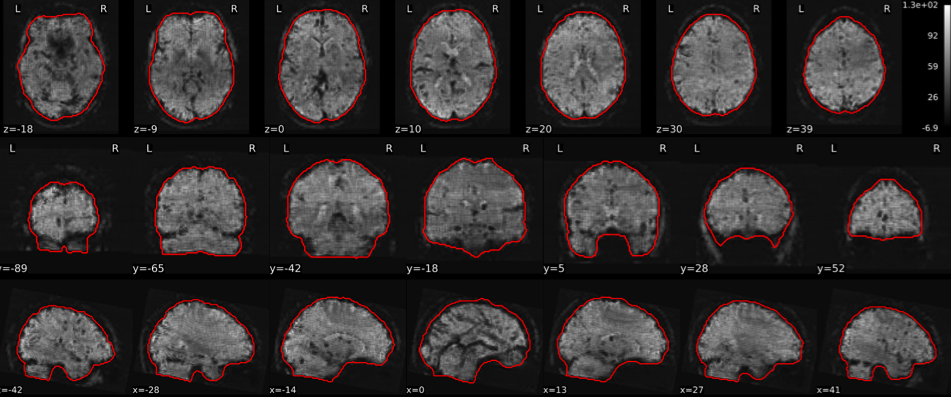

EPI tSNR

In the signal to noise ratio images of the resting state image the desired signal is compared to the amount of background noise. It is important to check all the views (sagittal, coronal, axial) because some artefacts (e.g., stripes) may be evident only in one particular view.

Example of a good subject

- Signal to noise is symmetrically distributed and there is no signal distortion

Example of a bad subject

- Asymmetry

- Potential signal distortion (might represent an artefact)

- Signal drop-out

- Stripes artefact

Clear large artefact (e.g., zebra stripes in example 1) are worth the exclusion of the subject. If you are unsure, check the other quality metrics for that subject to decide whether they should be excluded.

Summary

| good | bad |

|---|---|

| Symmetrical distribution of noise and signal | Asymmetry |

| No disruptions of the signal (no “black patches”) |

Potential signal disruptions (could be related to artefacts) |

| No stripes (sign of high motion) |

Signal drop |

| Stripe artefacts (“zebra” stripes due to motion) |